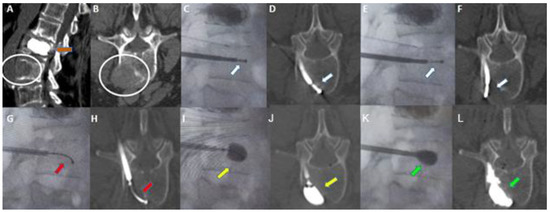

Figure 3. Sixty-eight-year-old woman with a history of breast cancer. (A,B): Sagittal (A) and axial (B) contrast-enhanced CT scan showing a metastatic lytic lesion of the left anterolateral portion of the L3 vertebra extending to adjacent perivertebral soft tissues (white circle in (A,B)). Previous vertebral augmentation treatment with Arcadia in L2 (orange arrow in (A)). (C,D): Fluoroscopy in the lateral plane (C) and axial CT scan (D). Placement of the STAR™ radiofrequency probe (white arrow) in the central portion of the lesion. (E,F): Fluoroscopy in the lateral plane (E) and axial CT scan (F). Placement of the STAR™ Radiofrequency steerable probe (white arrow) in the lateral aspect of the lesion. (G,H): Fluoroscopy in the lateral plane (G) and axial CT (H). Arcadia™ low compliance high pressure steerable balloon was inserted coaxially into the introducer cannula and deployed into the lesion (red arrow). (I,J): Fluoroscopy in the lateral plane (I) and axial CT (J). Arcadia™ low compliance high pressure steerable balloon gently inflated with a mixture of saline and iodinated contrast, with the intent of compacting the ablated tissue and creating a void for cement delivery (yellow arrow). (K,L): Fluoroscopy in the lateral plane (K) and axial CT (L). StabiliT® high viscosity bone cement was slowly delivered into the lesion for the stabilization of the vertebral body (green arrow).